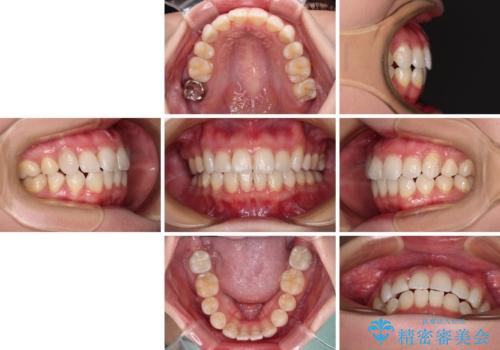

上顎の八重歯と下顎前歯の欠損 ワイヤー装置による抜歯矯正

- 上顎の八重歯を気にして来院された患者様です。

診察したところ、下顎前歯が2本欠損していたため、上下のバランスを取りながら八重歯を改善するため、上顎左右第一小臼歯2本を抜歯することとしました。

下顎左右大臼歯の歯根部に病変があったため、矯正治療前に根管治療を行い、矯正治療後にセラミッククラウンによる補綴治療を行うこととしました。

下顎前歯と本来抜歯矯正で抜歯する歯とは大きさが異なるため、仕上がりの咬み合わせは理想的なものとはなりませんでしたが、気になっていた八重歯はきれいに改善することができました。